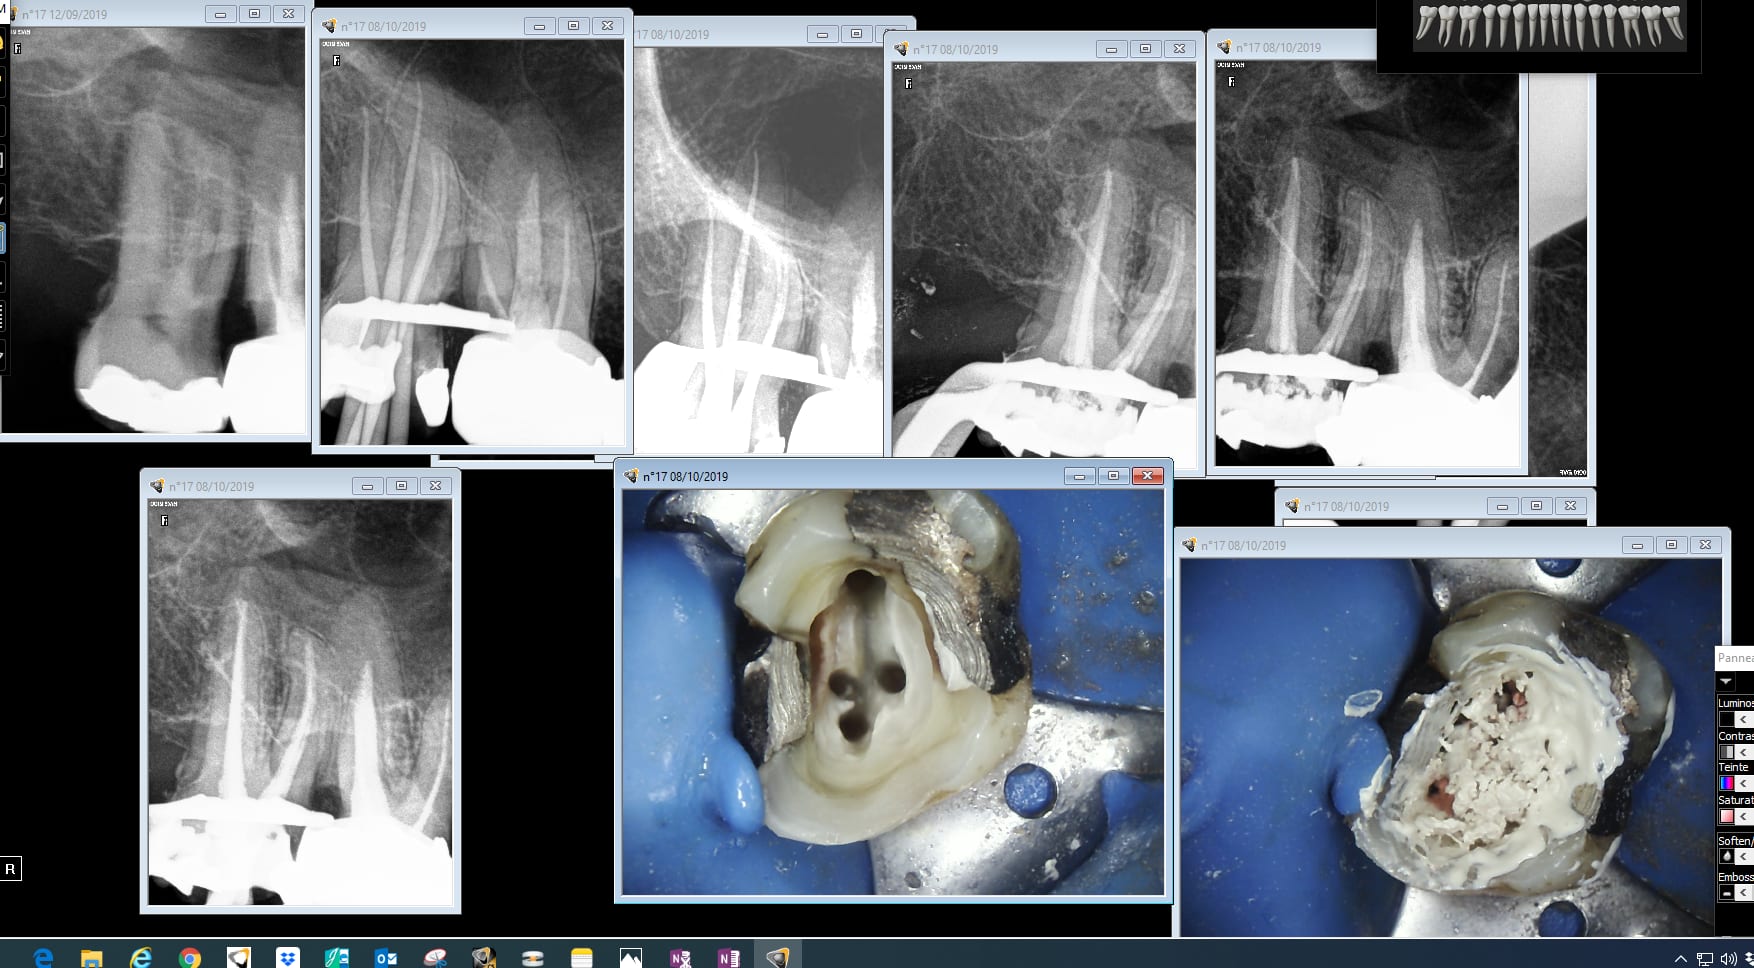

Ca dépend quelle endo molaire. Je te rappelle que tu es obligé de travailler selon les données actuelles de la science. -)))

Sans déconner j'espère qu'ils vont contrôler toutes les endos. Il y en a qui feront moins les malins.